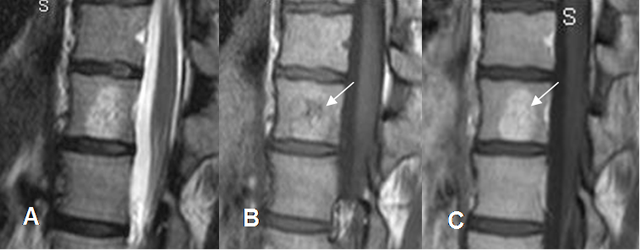

Fig 152. Hemangioma óseo.

A: RM sagital en T2, B: RM sagital en T1 simple y C: RM sagital en T1 con contraste.

Lesión hiperintensa en ambas secuencias. La parte superior en T1 es hipointensa y realza con el contraste. (Flechas).